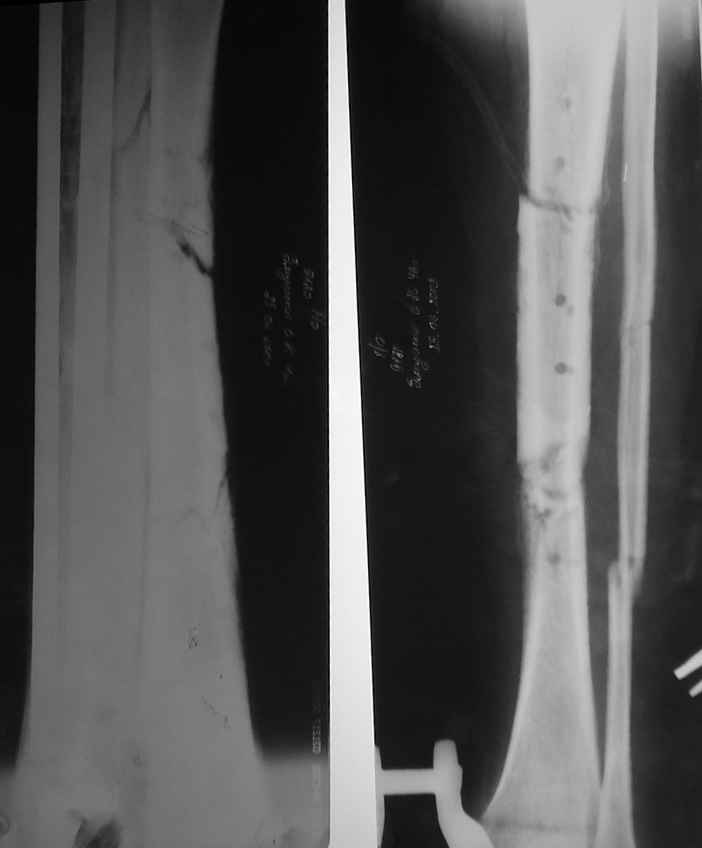

В настоящее время целостность мягких тканей голени полностью восстановлена, кожные лоскуты на мышце розовые фиксированные, раны закрыты на 100%, больной активен, ходит на костылях с дозированной нагрузкой на ногу в аппарате. Планируем выписать его на месяц по месту жительства. И если не получится с Минском, сделаем ему как и планнировали что-то вроде операции Гана-Кодивилла-Геттингтона. Пациент заранее настроен на длительное лечение в аппарате Иллизарова, уже хорошо адаптирован,оптимистичен и пока очень доволен результатами, отмечает значительное улучшение самочувствия. В приложении высылаю фотографии рентгенограм до и после операции.

В приложении рентгенограмма через год после операции.